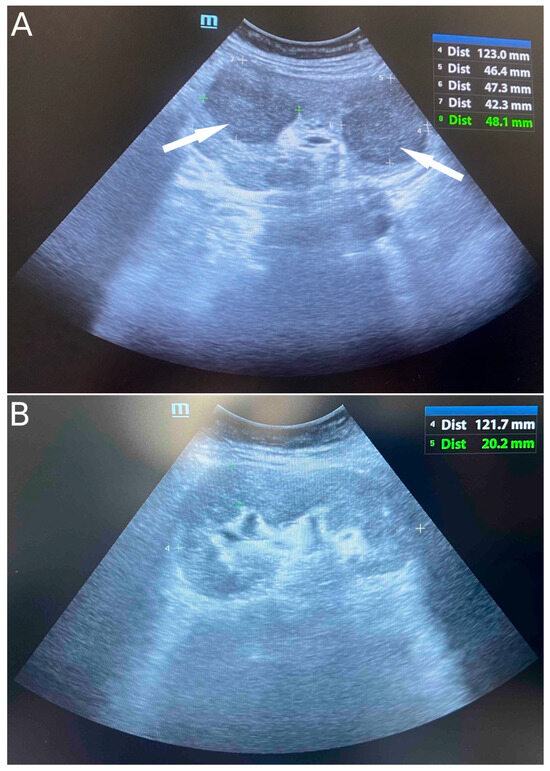

2. Case Presentation